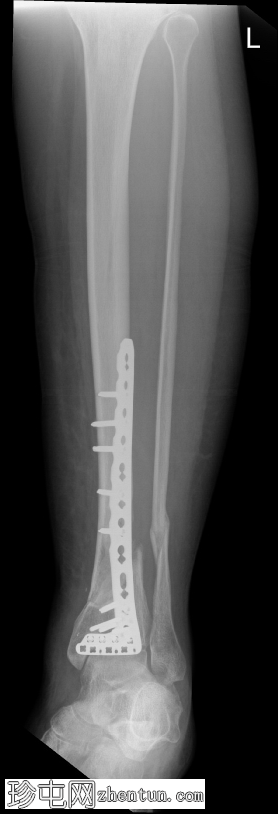

X线片

1.png

侧位片

可见胫骨远端前内侧支撑钢板,并有多枚螺钉固定,与既往胫骨远端骨折切开复位内固定术(ORIF)相符。

数枚远端螺钉断裂,钢板远端与胫骨远端骨膜表面分离,提示钢板与骨骼接触不良,可能存在内固定松动或部分机械失效。其余螺钉及钢板近端部分完整,对位良好。

胫骨远端内侧可见一小块骨化良好的骨碎片,密度与邻近骨皮质相似,提示为既往骨折残留碎片,而非急性骨折碎片。

骨折部位显示部分愈合,胫骨和腓骨整体对位良好。踝关节间隙保持正常。未发现新的骨折、脱位或骨膜反应。

无既往X线片可供对比。